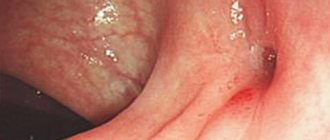

A doctor can detect a tumor during a digital rectal examination, anoscopy (which can be difficult if the tumor is large), or during an endoscopic ultrasound examination. The effectiveness of treatment depends on the stage of the disease, which is why it is so important to know the first signs of anal cancer that you should pay attention to.

Anal cancer

Cancer of the anus and anal canal corresponds to a wide range of different histological forms, which is determined by the complexity of the structure of the anal area, as well as the variety of types of epithelial tissues. The most common form of anal cancer is squamous cell, also known as epidermoid cancer of the anus - about 55% of all cases. It develops somewhat distal to the rectal-anal line, namely from the external tissues of the anus, and subsequently it becomes predisposed to the formation of ulcers. The cloacogenic type of anal canal cancer is less common - 25-30%, and occurs in the transition zone between columnar epithelium and squamous epithelium. Adenocarcinoma is of glandular origin, and melanoma is of skin and mucosal cells.